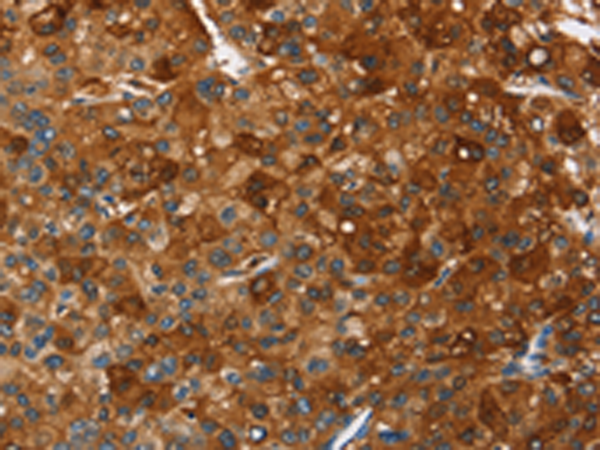

分类: 科研抗体货号: P07530别名: TFAR19应用: IHC反应种属: Human, Mouse